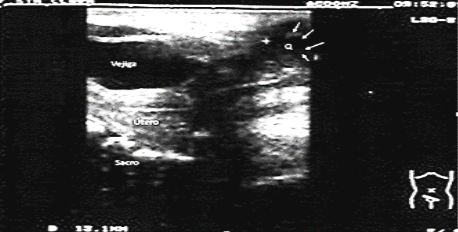

El ultrasonido abdominal resulta normal, el ultrasonido ginecológico no demuestra alteraciones uterinas descartándose la posibilidad de hidrometrocolpos; observándose hacia la región más distal una imagen ecolúcida, quística, bien circunscrita que mide 11.5 x 11.7 mm. (Figuras 1 y 2)

Fig. 1 Ultrasonido suprapúbico con transductor de 8 MZ visualizándose vejiga, vagina (vag), útero y la imagen quística distal (Q)

Fig. 2 Ultrasonido suprapúbico con transductor de 8 MZ visualizándose vejiga, útero, sacro y la imagen quística distal (Q-con flechas blancas).